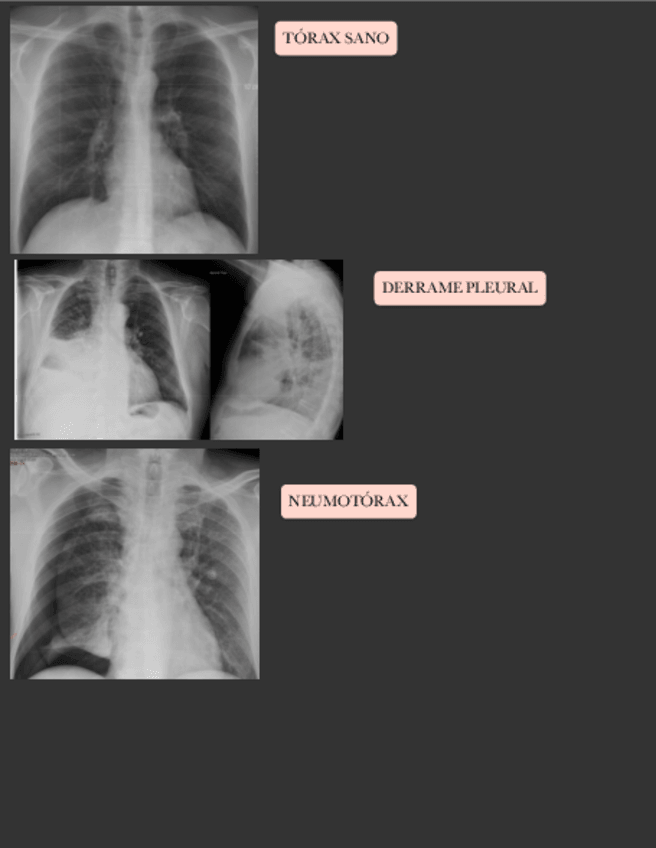

He publicado nuevos apuntes de 3º Radiología y Medicina Física. Protección Radiológica: IMAGENES-RAYOS-TORAX.pdf